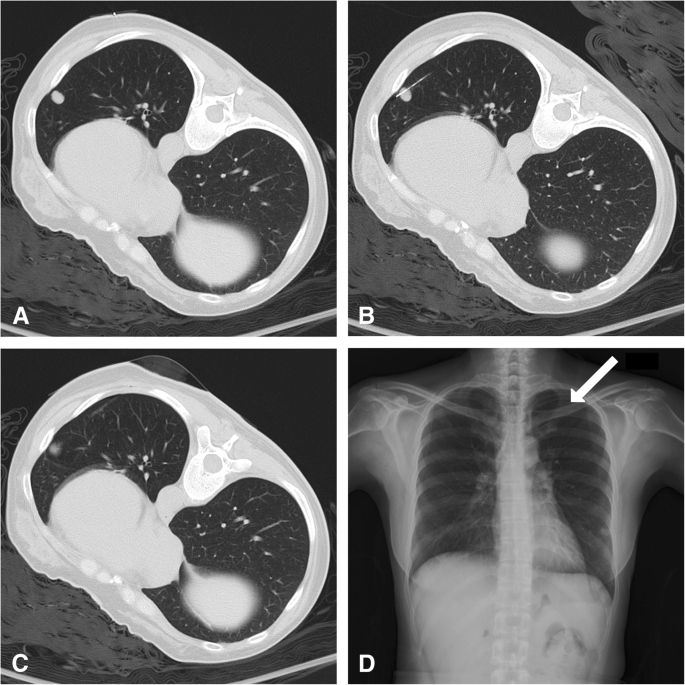

The method used depends on where the sample will be taken from and your overall health. A lighted tool called a bronchoscope is inserted through the. A guide needle was inserted into the mass and 2 fine needle aspirations were performed.

After the fine needle aspirations 6 core biopsies were obtained. A postprocedure CT was performed.